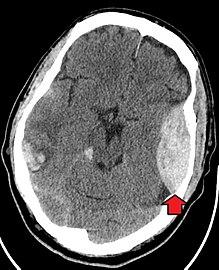

Blunt cranial trauma

The primary clinical concern with blunt trauma to the head is damage to the brain, although other structures, including the skull, face, orbits, and neck are also at risk.[9] Following assessment of the patient's airway, circulation, and breathing, a cervical collar may be placed if there is suspicion of trauma to the neck. Evaluation of blunt trauma to the head continues with the secondary survey for evidence of cranial trauma, including bruises, contusions, lacerations, and abrasions. In addition to noting external injury, a comprehensive neurologic exam is typically performed to assess for damage to the brain. Depending on the mechanism of injury and examination, a CT scan of the skull and brain may be ordered. This is typically done to assess for blood within the skull, or fracture of the skull bones.[18]

Traumatic brain injury

Traumatic brain injury (TBI) is a significant cause of morbidity and mortality and is most commonly caused by falls, motor vehicle accidents, sports- and work-related injuries, and assaults. It is the most common cause of death in patients under the age of 25. TBI is graded from mild to severe, with greater severity correlating with increased morbidity and mortality.[18][19]

Most patients with more severe traumatic brain injury have of a combination of intracranial injuries, which can include diffuse axonal injury, cerebral contusions, and intracranial bleeding, including subarachnoid hemorrhage, subdural hematoma, epidural hematoma, and intraparenchymal hemorrhage.[9] [18] The recovery of brain function following a traumatic accident is highly variable and depends upon the specific intracranial injuries that occur, however there is significant correlation between the severity of the initial insult as well as the level of neurologic function during the initial assessment and the level of lasting neurologic deficits.[18] Initial treatment may be targeted at reducing the intracranial pressure if there is concern for swelling or bleeding within this skull, which may require surgery such as a hemicraniectomy, in which part of the skull is removed.[9][18]